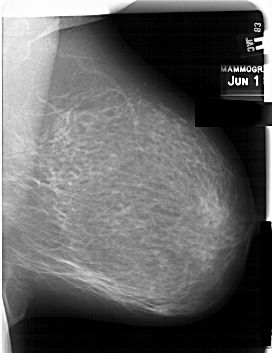

A_1560_1.LEFT_MLO

LEFT_MLO LINES 6346 PIXELS_PER_LINE 5266 BITS_PER_PIXEL 12 RESOLUTION 43.5 OVERLAY